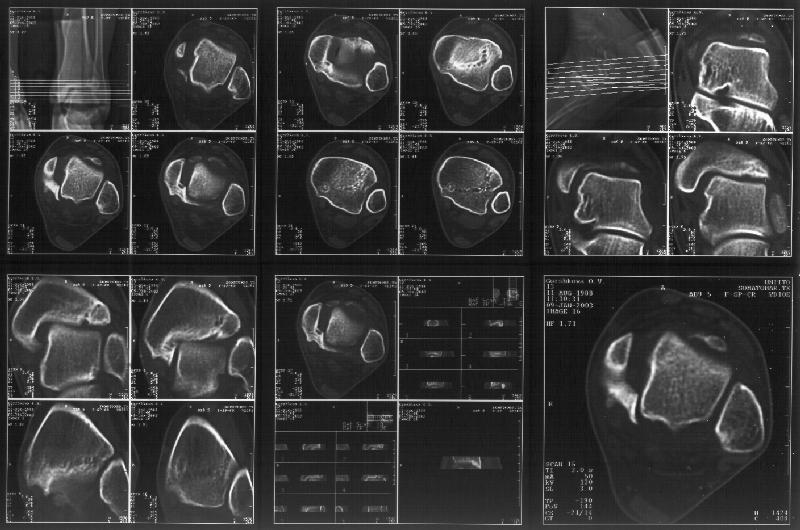

На следующий день пациентке сделали КТ. Может быть, после просмотра картинки будут другие предложения? Не убрать ли ве-таки этот фрагмент

позади внутренней лодыжки, который оттесняет таран кнаружи?

Думаю, КТ прочитан не верно. Задняя часть медиального маллеола, в сущности уже часть заднего маллеола стоит на месте и трогать её не следует. Передняя часть маллеола на 3-4 мм удалена от тарана. Сравните с пространством между

латеральным маллеолом и тараном. В норме все три должны быть одинаковы: между тараном и латеральным, задним и медиальным. Это главное условие устойчивого сидения тарана в голеностопном суставе.

Все-таки она как раз была была отколота и вместе с тараном смещена латерально.

Внутренняя лодыжка не была сломана, она как была на своем месте, так там и находится. Это таран от нее отдавлен кнаружи смщенным в его сторону фрагментом позади внутренней лодыжки. За счет чего и есть проявления нестабильности связок.

Здесь 4 среза, начиная от основания лодыжки и проксимальнее. Где, по Вашему мнению, проходит линия перелома, отделяющая переднюю часть внутренней лодыжки от большеберцовой кости? Заранее спасибо.

Я пометил линию перелома черной линией.

К сожалению на последних присланных срезах КТ нет более низкого, через таран, среза, который был на прежнем майле. На XR я попытался показать

стержень внутри сустава и то как он раскрывает пространство между тараном и мед. малеолом.

Сегодня пациентке сделали сравнительную КТ. А ксиальные и Фронтальные срезы приложены. Ваше мнение?

Фронтальные

Аксиальные

Отправитель: Й. Воск 19 Январь 2003, 22:50

На КТ я попытался изобразить скромными своими способностями (А)- место перелома, (С)- нормальный суставной зазор меж тараном и тремя его маллеолами. (В)- образовавшийся в результате перелома широкий раза в три зазор, позволяющий, по-моему, сублюксацию тарана при ходьбе. В свете данных КТ, критически важных, я бы предложил вертикальную остеотомию места перелома

задне-внутренним подходом и фиксацию мед. маллеола прижатым к тарану с помощью тонкого compression screw. После этого гипсовый сапожок и немедленное расхаживание ноги.